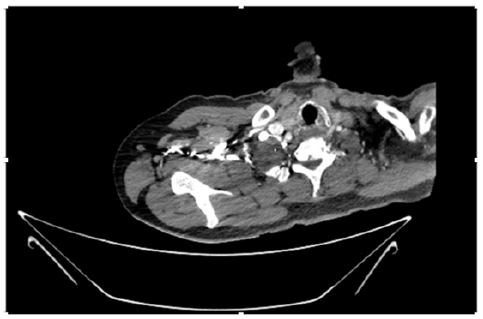

55-years-old chronic smoker had acute, severe pain in the right upper limb for one week; it was cold upto mid arm with skin discoloration. He also noticed numbness and weakness of movement of elbow joint. He underwent below elbow amputation in February 2023 for acute ischemia of left upper limb. He was a current chronic smoker; 15 pack year. General condition was weak; temperature was normal; blood pressure was 100/60mmHg; heart rate was 92/minutes with sinus rhythm; SpO2 was 97% on air; heart was normal. In lower extremities, all peripheral pulses were intact. Local Examination of right upper limb revealed as follows: tenderness; coldness; discoloration; decreased motor function and sensory modalities. Axillary, brachial and radial pulses were not palpable. Hand-held Doppler failed to detect any signal in arterial system; therefore, we arranged for emergency embolectomy. complete occlusion of right upper limb arterial system Full blood count showed high hemoglobin (14.6gm%); normal total WBC and platelet count. Coagulation profile was normal. Parenteral unfractionated heparin, antibiotics, tramadol, proton-pump inhibitors, anti-platelets and HMG CoA reductase inhibitors were given. Doppler ultrasound demonstrated complete occlusion of right upper limb arterial system. CT Angiogram illustrated occlusion of subclavian artery downwards on both sides. Figures 1-14 shows complete occlusion of right subclavian artery without collaterals. On Day ‘2’ of admission, the patient passed black tarry stool for 3 times. However, the vital signs were stable; blood pressure was 100/60mmHg; heart rate was 92/min; SpO2 was 97% on air; the abdomen was soft and not tender. Above elbow amputation was done on Day ‘2’ of admission. Intra-operative findings were as follows: (1) no active bleeding at brachial artery; (2) thrombosis along brachial artery; (3) muscle color and consistency were not healthy.

Figure 4: CT Angiogram at neck showing normal brachio-cephalic trunk, common carotid artery, and narrow right subclavian artery.

Figure 5: CT Angiogram at neck showing normal brachio-cephalic trunk, common carotid artery, and narrow right subclavian artery.

Figure 6: CT Angiogram at neck showing brachio-cephalic trunk, common carotid artery and narrow right subclavian artery.

Figure 7: CT Angiogram at neck showing brachio-cephalic trunk, common carotid artery and narrow right subclavian artery.